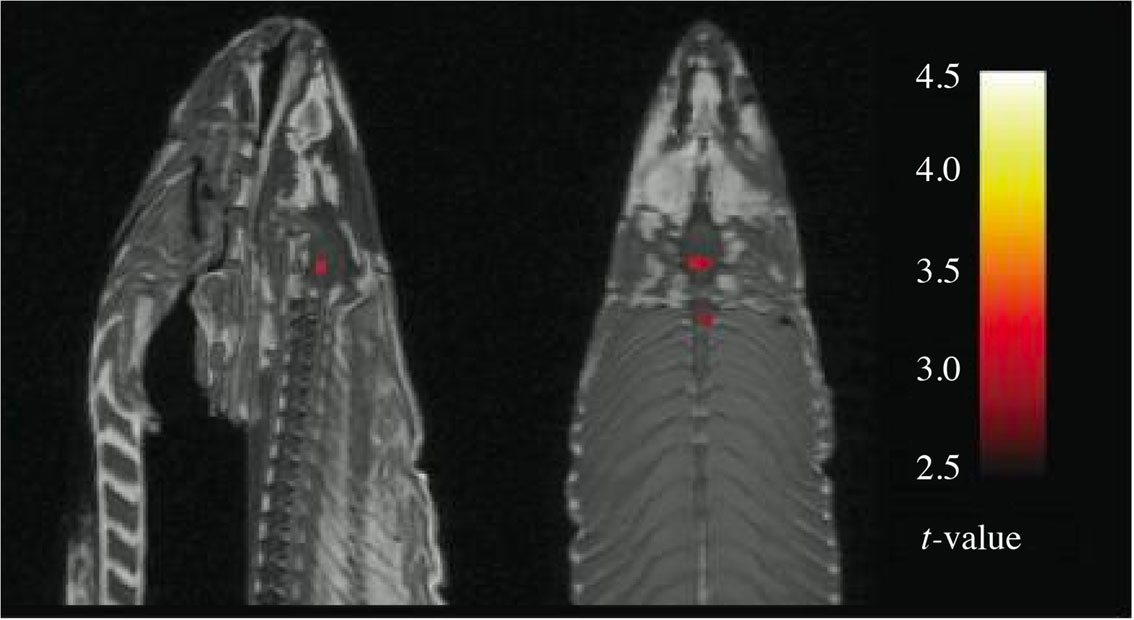

Jo Røislien skriver at bildet av den døde laksen viste «tre statistisk signifikante prikker» (1).

Begrepet «statistisk signifikant» er vanligvis knyttet til en p-verdi. I dette tilfellet synes imidlertid ordet «signifikant» å være knyttet til en t-verdi. T-verdier er en form for kvantifisering av forskjeller, altså et litt komplisert effektestimat som er uavhengig av antall observasjoner. P-verdien derimot, er sterkt avhengig av antallet slik at ubetydelige forskjeller blir signifikante bare antallet observasjoner er stort.